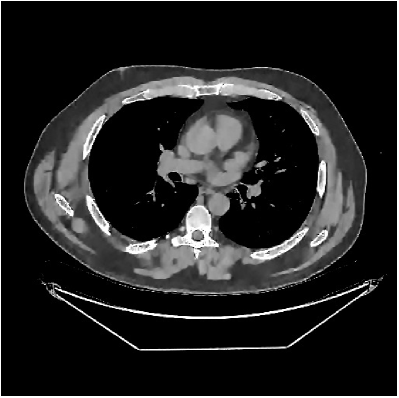

This section compares the reconstruction quality and runtime among the proposed MBIR method, PWLS-ST-, and other three MBIR methods, PWLS-EP, PWLS-DL, and PWLS-ST-. Table I shows that, for both 2D and 3D sparse-view CT reconstructions of the XCAT phantom, the proposed PWLS-ST- model outperforms PWLS-EP and PWLS-ST- in terms of RMSE. In addition, PWLS-ST- using a square transform (of size ) achieves lower RMSE than PWLS-DL using an overcomplete dictionary (of size ) for 2D sparse-view reconstructions. Fig. 3(a) and Fig. 4 show the reconstructed images for 2D and 3D phantom experiments, with different reconstruction models and different number of views. (See the corresponding error maps in the supplement.) The proposed PWLS-ST- consistently gives more accurate image reconstructions compared to other MBIR methods. Specifically, PWLS-ST- has smaller errors in the heart region (see zoom-ins in Fig. 3(a)) of 2D reconstructions than PWLS-DL and PWLS-ST-. In addition, compared to PWLS-ST-, PWLS-DL and PWLS-ST- have some ringing artifacts around the edges with high transition, e.g., edges between air and soft tissues. (See a comparison of profiles of PWLS-ST- and PWLS-ST- in the supplement.) In particular, PWLS-ST- and PWLS-DL give more visible ringing artifacts for 2D reconstruction from fewer views, and PWLS-ST- has these ringing artifacts for 3D reconstructions regardless of the number of views (see zoom-ins in Fig. 4). Table II reports runtimes of different MBIR methods in reconstructing the -views XCAT phantom scan. (FBPConvNet is a non-MBIR method and its runtime for processing a image is approximately one second with a TITAN Xp GPU.) While providing better reconstruction quality, the proposed Algorithm 1 of PWLS-ST- has shorter runtime compared to the algorithms of PWLS-DL and PWLS-ST- in Section III-A. Similar to the PWLS-EP algorithm, the reconstruction time of the PWLS-DL, PWLS-ST-, and PWLS-ST- algorithms can be further reduced by using ordered subsets [51].

Fig. 3(b) shows that when tested on the clinical scan data, the proposed PWLS-ST- method improves reconstruction quality in terms of noise and artifacts removal (e.g., see zoom-ins for soft-issue regions), and edge preservation (e.g., see zoom-ins for bone regions), compared to PWLS-EP and PWLS-ST-. Compared to PWLS-DL, PWLS-ST- achieves comparable image quality, but requires less computational complexity.

![]() |

| (a) 2D fan-beam CT experiments |

| (b) 3D axial cone-beam CT experiments |